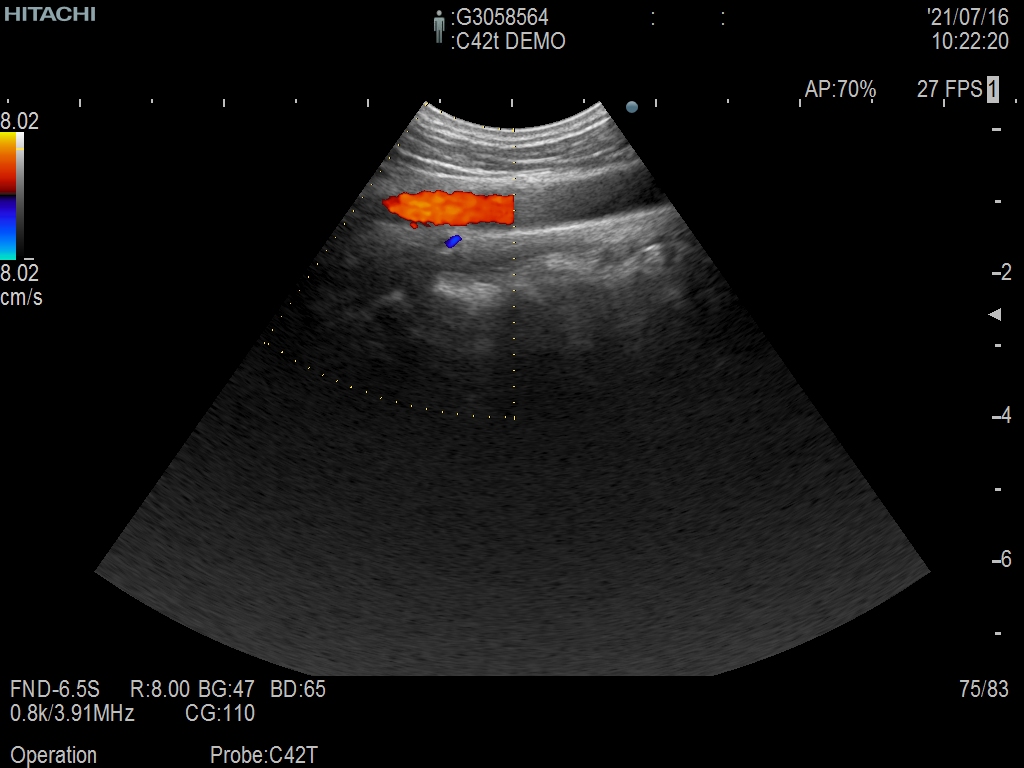

Hitachi C42T Ref Intraoperative Convex – ARIETTA

ARIETTA Convex C42T Intraoperative

Intraoperative Finger-grip T-Style

10 – 3 MHz

Hitachi C42T Intraoperative Convex – ARIETTA

Frequency Range: 10 – 3 MHz

Scan Width: 20 mm Radius

Scan Angle: 65° FOV

Hitachi C42T Intraoperative Convex – ARIETTA for Intraoperative Finger-grip Convex T-Style

| Ακτινολογικές λειτουργίες | Contrast Harmonic Imaging (CHI), Elastography (RTE), RT Sonography (RVS) |